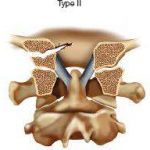

46歲男性單車手倒下導致頭顱枕骨髁骨骨折和頸椎C1-2韌帶損傷

他的頭顱和頸脊柱都不穩定, 由於頸椎神經損傷引起的手臂暫時性麻木